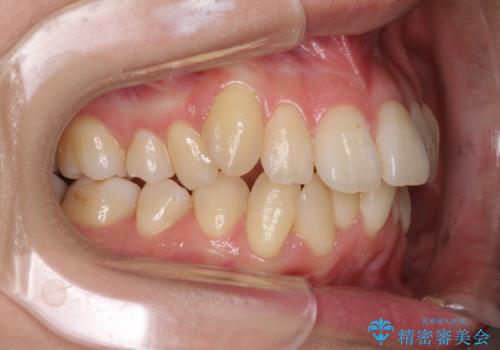

インビザラインを用い、IPR(歯と歯の間を削る)と歯列全体を後方に移動させることで、歯並びを整えていくこととしました。

歯列全体を後方に移動させるため、下顎の親知らず2本を抜歯することとしました。

突出した印象のあった前歯をきれいに引っ込めることができたので、口が閉じやすくなり、横顔の印象をスッキリとさせることができました。